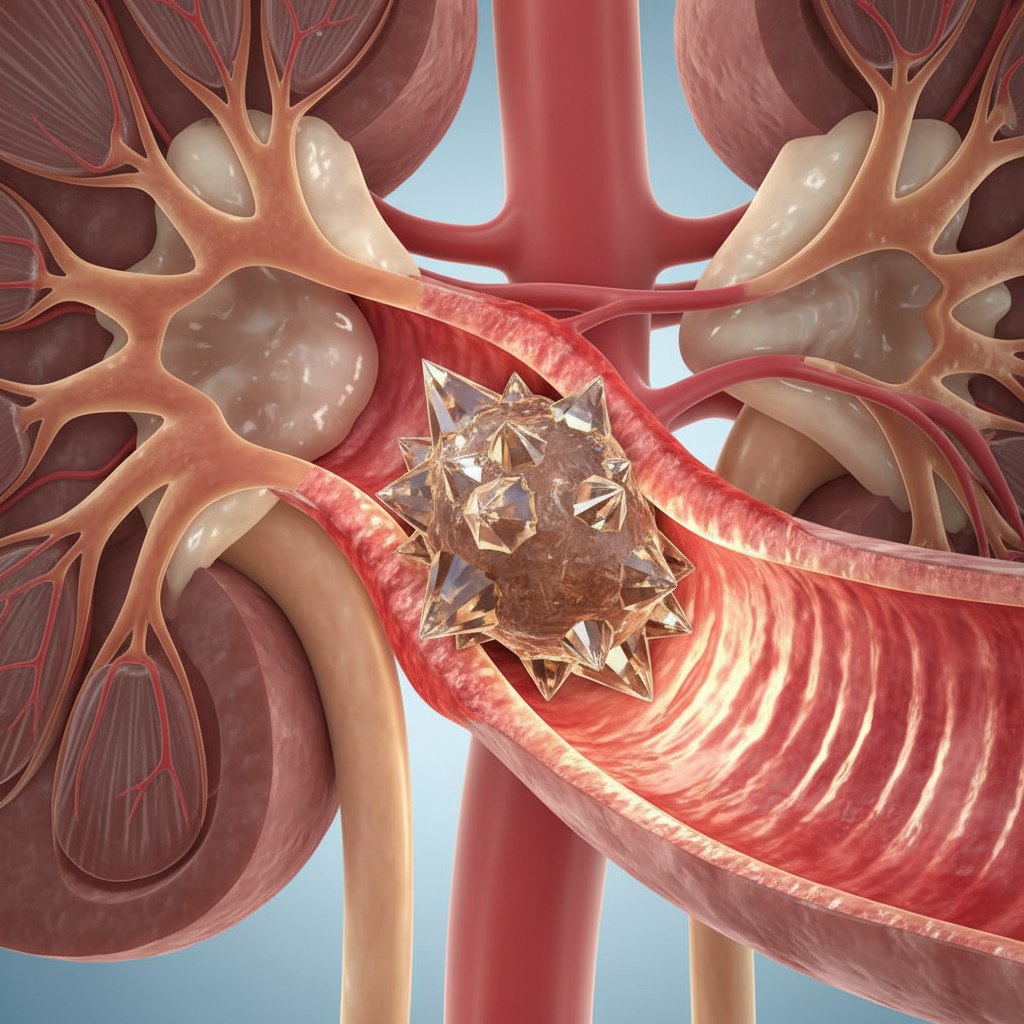

가장 대표적인 질환은 '요로결석'입니다. 소변 속의 찌꺼기들이 뭉쳐서 돌(결석)이 되고, 이 돌이 좁은 요관을 타고 내려오다가 상처를 내거나 소변 길을 막으면서 발생합니다. 산통에 비유될 정도로 끔찍하고 갑작스러운 통증이 옆구리에서 시작해 아랫배나 사타구니 쪽으로 뻗어나가는 특징이 있어요. 통증이 너무 심해서 식은땀을 흘리거나 구역질을 동반하기도 합니다.